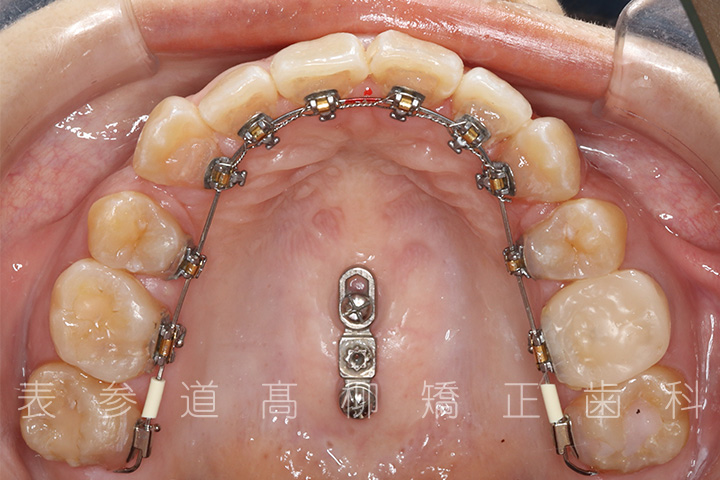

・金属アレルギーのため、マウスピース型矯正装置を多く設定し、ワイヤーでの矯正治療期間を短縮

・マウスピース型矯正装置と歯科矯正用アンカースクリュー(i-station)を併用し、上顎臼歯部を圧下

・歯科矯正用アンカースクリュー(i-station)を併用し、前歯部を後方へ移動する

・歯科矯正用アンカースクリューを併用し、口下顎大臼歯の近心移動(前方への移動)

・上下歯列の緊密な咬合関係の確立に顎間ゴムを併用(装着時間20時間以上/日)

・マウスピース型矯正装置

・リンガルブラケット装置

・歯科矯正用アンカースクリュー